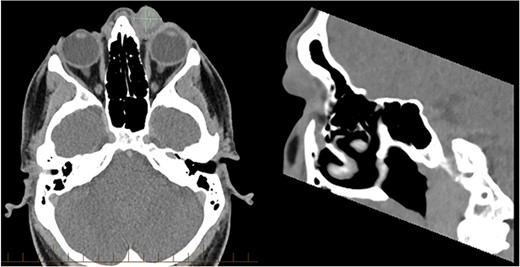

Computerised tomography (CT) and magnetic resonance imaging (MRI) were performed to further define the lesion as seen in Figs 1 and 2.

MRI of the orbits demonstrated a 20 × 18 mm well defined rounded mass arising within the medial canthus with no infiltration or bony erosion.